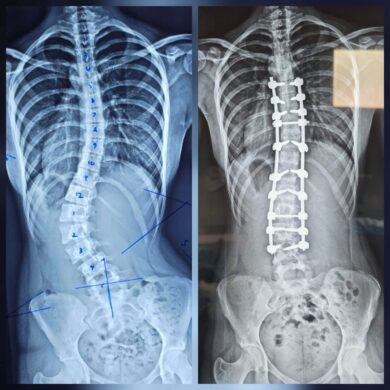

புத்தளம் தள வைத்தியசாலையில் இடம்பெற்ற

முள்ளந்தண்டு நேராக்கல் (Scoliosis Correction) சத்திரசிகிச்சைபுத்தளம் தள வைத்தியசாலையில் இடம்பெற்ற முள்ளந்தண்டு நேராக்கல் (Scoliosis…